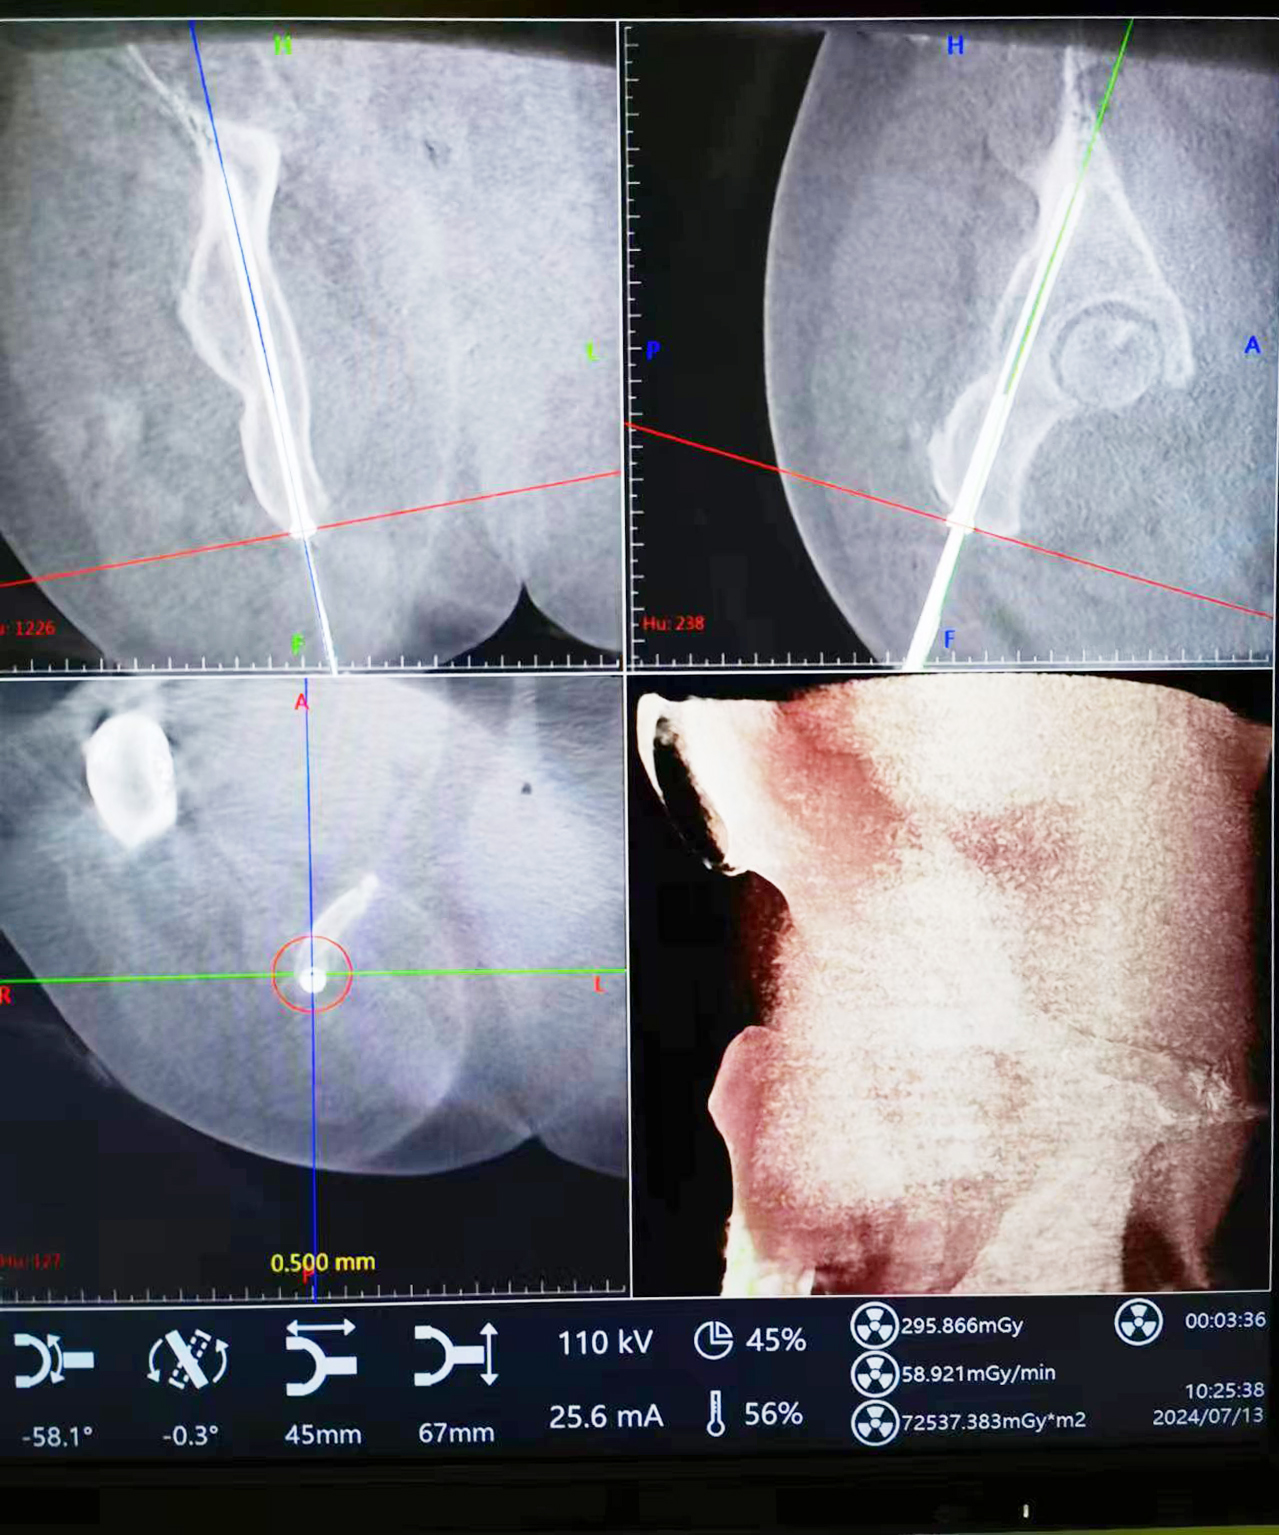

術(shù)中將示蹤器用克氏針固定于患側(cè)髂后上棘,將采集到的圖像傳輸至主控臺用于對骨盆通道螺釘進行路徑規(guī)劃,選擇螺釘直徑、長度、入點、止點。在遙控導(dǎo)航下,機器人將機械臂沿著規(guī)劃路徑移動到目標(biāo)位置,置入導(dǎo)針和螺釘。術(shù)中驗證髖臼后柱螺釘置入位置精準(zhǔn),切口1.0cm。